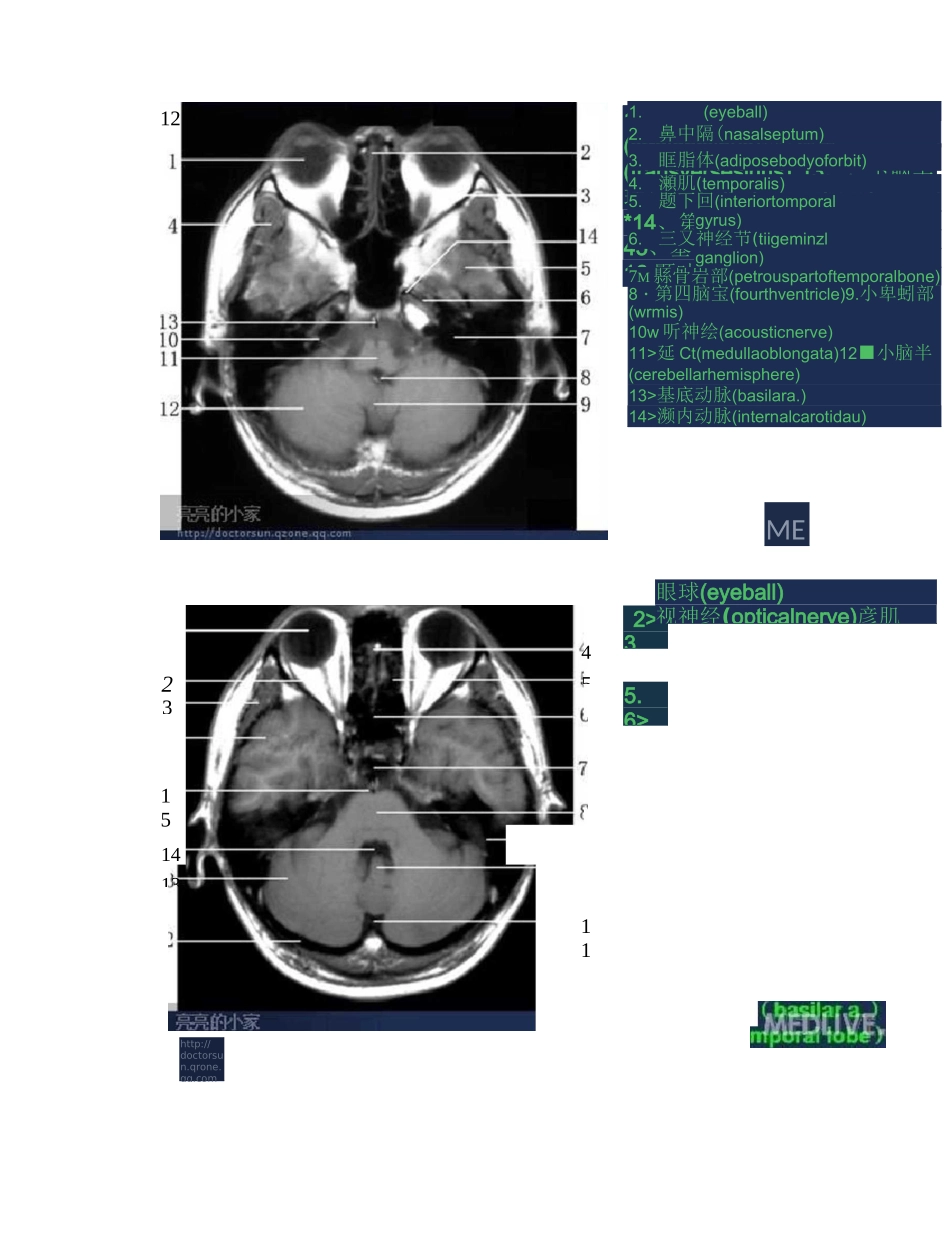

全身 MRI 图谱12.上頓寞(muHlary*inuft)整釧璋 FKttp^/d^ct^ruu 怕■屜 GW 靳qqwn8910rJ67仏鼻中驕(nasalseptum)2.*鼻甲(middleconcha>3.延謄体(adiposebodyoforbit)4.鼻外肌(lateralptergoid)5•顔肌(temporalis}6.理寞(Ephenoidalsinus)I.三戈神经节(trigEEiwtganglion)8«基底动蘇(basilara.)9,A&flL(medLIIIdobkngata>勺队小(cerebellarhemisphere)II.厳肯岩娜(petrousp^rtoftemporalbone)霸內卜家http:/^dactarE-un.qzgnE.qgFcearnN3.10111213氐6・7.8.9,鑽上倒(stipBriarfrontalgyrus)并攵射局(coronaradiatat 中夬都顿上回(superiorfrontalgyrus)2•额中回(middlefrontalgyrus)3w 放冠(coronaradiata)4.侧脑室三角(triconeoflateralventricle)5.侧脑定下斤(inferiorhornoflateralventricle)6.小脑蚓部(vermis)7.小脑半(cerebellarhemisphere)8<上矢状釜(superiorsagittalsinus)9n 瞬脈体(corpuscallosum)10.松果体(pinealbody)11.願中回(middletemporalgyrus)12.小脑延《l 池https//doctorsun.qzone,qq,com頭®卜家http://doctorsun・qzone・qq・uam5678910111213143.4.5.7.9.10>11.12.放射冠(coronaradiala)硕上回(superiortemporalgyrus)願中曲(middletemporalgyrus)小脑中脚(middlecerebellarpeduncle)上矢拓窦(superiorsagittalsinus)额上回(superiorfrontalgyrus)額中回(middlefroiitafigyrus)駢底体(corpuscallosum)狽 1 脑室中央璋(centralpartoflateralventricle)第三肘童(thirdventricle)中脑(midbrain)海马旁回(parahippocampalgyrus)小脑于球(cerebellarhemisphere)体巒岬护 WE.CNoolonggaia)MEDLI2>3.5.6>7>8、眼球(eyeball)视神经(opticalnerve)彦肌10.小脑蚓部(vermis)*14、直窦(straightsinus)12M 横婁(transversesinus)*13、,卜脑半球(cerebellarhemisphere)*14、第四脑室(fourthventricle)45、基•庶^动脉 AB|i16.顯叶(t©1.(eyeball)2.鼻中隔(nasalseptum)3.眶脂体(adiposebodyoforbit)4.瀬肌(temporalis)5.题下回(interiortomporalgyrus)6.三又神经节(tiigeminzlganglion)7M 縣...